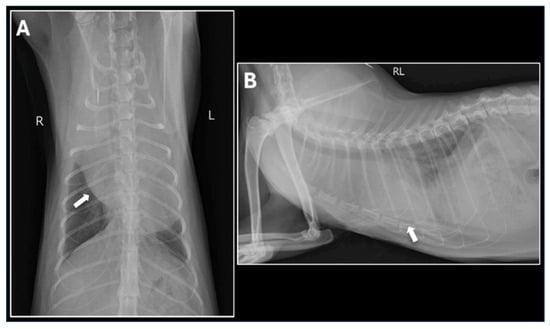

2.1. Initial Presentation and Clinical Findings

2.2. Referral and Diagnostic Evaluation